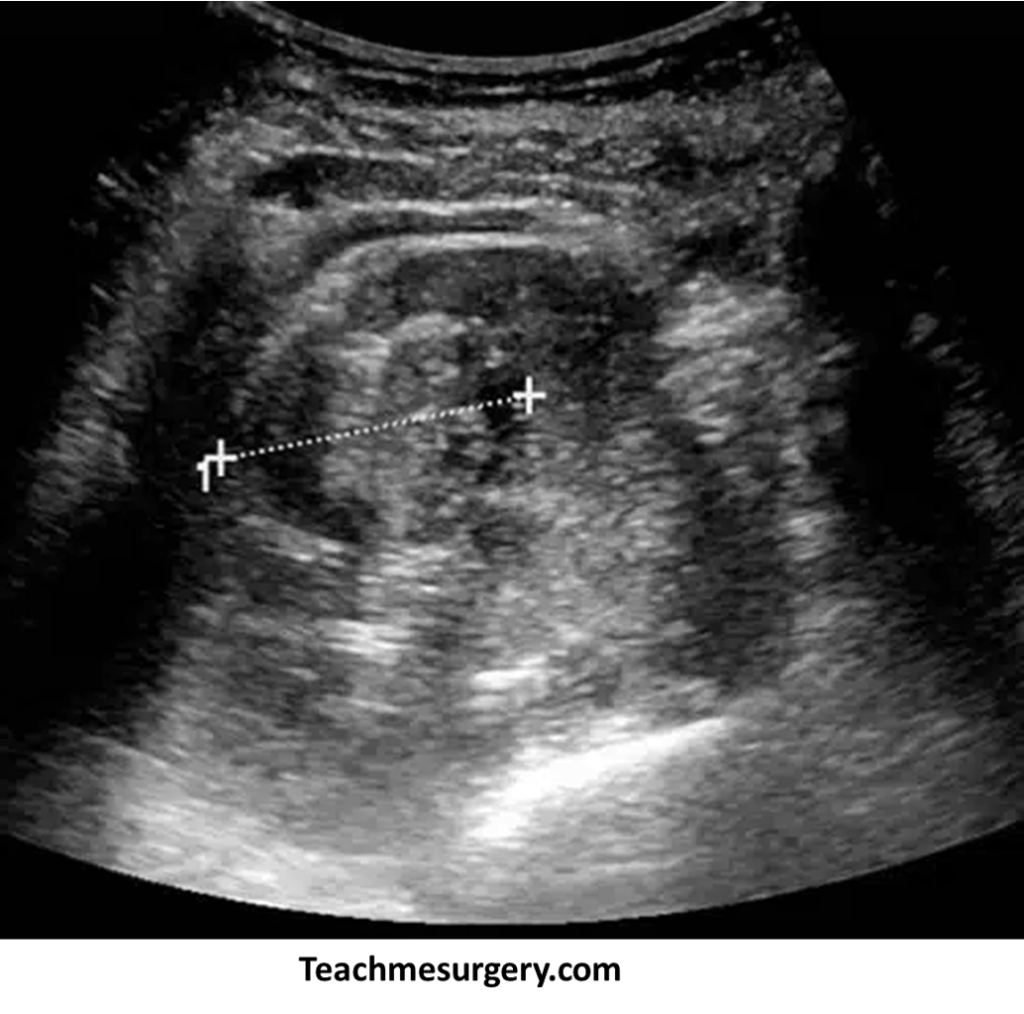

Imaging tests: Ultrasound Scan